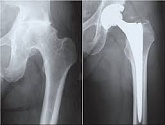

Еndoprosthesis of hip joint

In the late stages of arthrosis of the hip joint, medial fractures of the femoral neck in the older age group, the only way to recover is to replace the affected joint with an artificial joint - arthroplasty.

This method allows you to return the limb's limb, the full volume of movements in the affected joint, to save from constant pain and crunch during movements and, as a consequence, to return the patient to a full active life.

Below are presented X-ray photographs and photographs, illustrating the amount of motion in the affected joint before and after surgery.